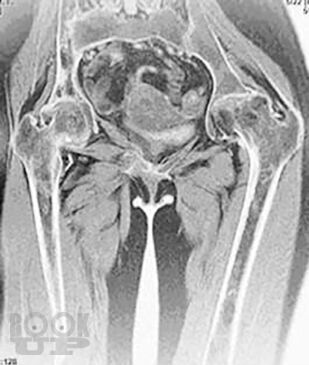

Болезнь Гоше относится к системным заболеваниям неопухолевой природы, в основе которых лежат наследственные дефекты метаболизма, приводящие к накоплению в органах и тканях нерасщепленных продуктов нормального обмена веществ. В случае болезни Гоше дефектом метаболизма является дефицит фермента, ответственного за метаболизм липидов.